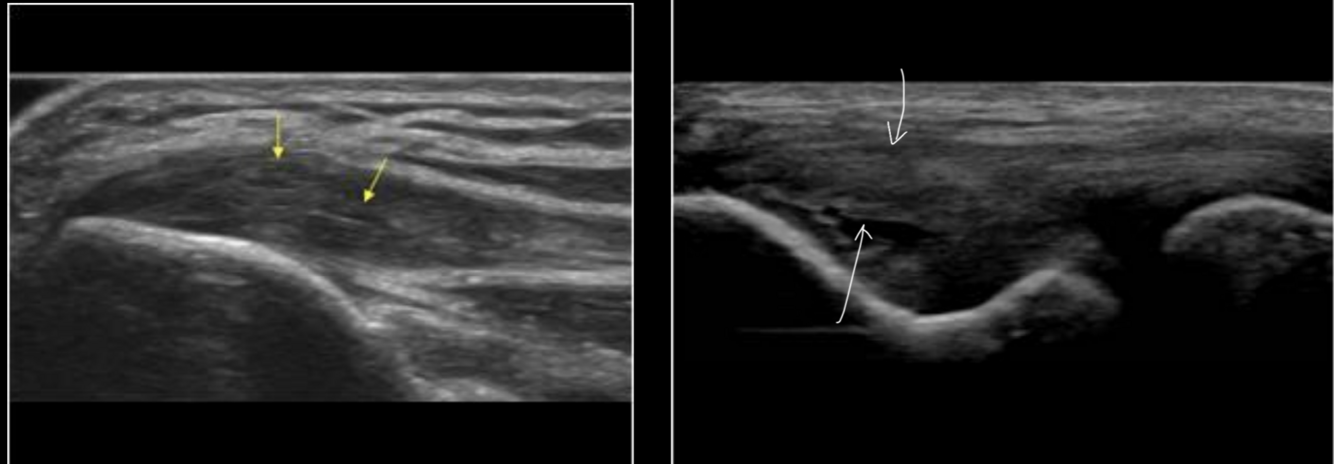

US Epicondylitis

Tendón engrosádo hipoecogenico

Epicondilitis